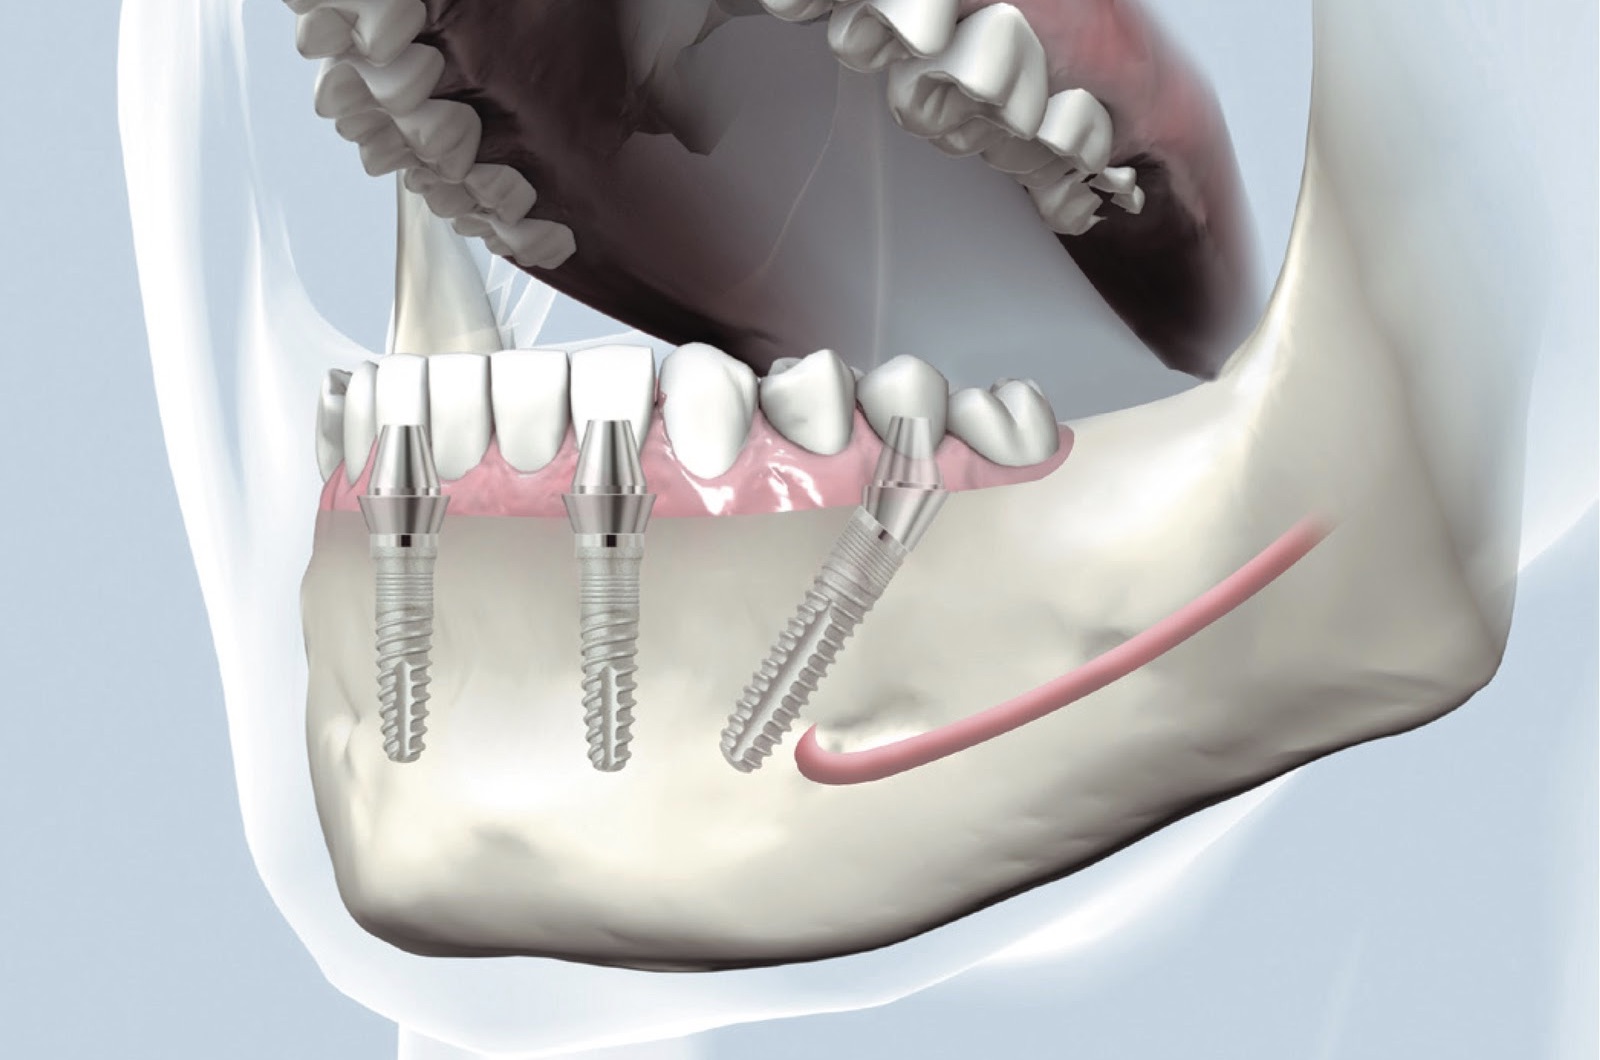

Современные методы протезирования зубов: Рекомендации и советы